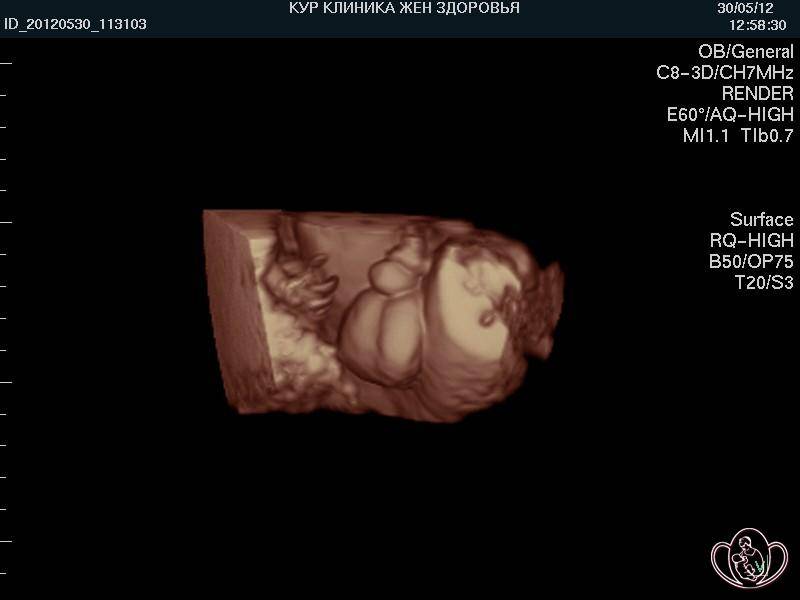

Что определяют на УЗИ

На 22-й неделе проводится второе скрининговое УЗИ, если оно не было назначено немного раньше. В отличие от первого скрининга, сейчас анализы крови не являются обязательными, если в прошлый раз не было выявлено риска рождения ребёнка с аномалиями развития. В ходе исследования врач определяет положение малыша в утробе. Оно может быть:

На 22-й неделе на УЗИ хорошо просматриваются контуры тела малыша

Оптимальным вариантом является головное предлежание, когда малыш занимает позицию головой вниз и вверх ножками. Если он сидит на попе или лежит на боку, не нужно расстраиваться, ведь ещё есть время и место в полости матки, чтобы перевернуться

Однако специалисты обращают внимание на положение плода уже сейчас. А также доктор изучает развитие жизненно важных органов, частей тела малыша, оценивает его рост и массу, соответствие гестационному сроку развития

Нормальными считаются следующие показатели:

- БПР (бипариетальный размер, измеряемый от одного до другого виска головы) – 48–60 мм;

- ОГ (окружность головы) – 64–76 мм;

- ОЖ (окружность живота) – 148–190 мм.

Оценивается также состояние матки на предмет тонуса, состояние и расположение плаценты, степень её зрелости

Немаловажное значением имеет количество околоплодных вод

На 22-й неделе на УЗИ хорошо видно, кого ждёт женщина, конечно, при условии доступного для датчика расположения половых органов плода

Все части лица уже хорошо сформированы. На глазках есть веки, которые приоткрываются. Выросли реснички и бровки, которые иногда хмурятся. Мимика ребенка пока не сознательна. Если сделать УЗИ в 22 недели, будет видно не только, что происходит с плодом, но и все его структуры лица. Причем, если малыш займет удобное для врача положение, уже можно будет понять, на кого из родителей он больше похож, чей у малыша рот или нос. На память можно будет сделать фото и видеозапись.

На этом сроке уже проводят допплерометрию — то есть смотрят состояние кровотоков ребенка. Если есть нарушения — может потребоваться стационарное лечение. Иногда нарушения бывают критическими, и тогда определяется значительная задержка развития плода, гипоксия. Обычно симптомом этого является медленный рост обхвата живота и высоты дна матки, а также слабые и редкие шевеления ребенка.

Если показания допплера нормальные, плод развивается согласно своему гестационному возрасту, прогноз на течение беременности и родов благоприятный.

При допплерометрии оценивается кровоток в артериях пуповины. Эти показания являются важнейшими характеризующими маточно-плодово-плацентарного кровообращения.

Кроме допплерометрии, на УЗИ в двадцать две недели гестации смотрят структуру плаценты. Она должна иметь однородную структуру. Возможно небольшое расширение межворсинчатых пространств. Данная особенность характерна для женщин, у которых часто бывает пониженным артериальное давление. Степень зрелости плаценты пока нулевая. Если врач ставит уже первую, это означает, что есть риск развития фетоплацентарной недостаточности, внутриутробной задержки развития плода. И, возможно, потребуется сделать перед третьим скрининговым УЗИ еще одно, контрольное, чтобы оценить кровотоки плода.